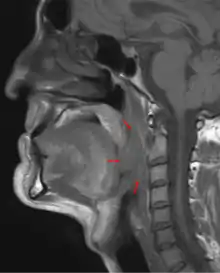

Oropharyngeal cancer (from right tonsil, HPV-negative), T4a N2c, 48-year-old man.

Diagnosis is by biopsy of observed abnormal tissue in the oropharynx.